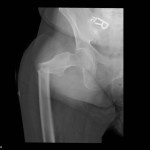

Hardware Complication – Dislocated left hip replacement hardware

Diagnosis: Dislocated left hip - hardware complication

Credit: Case submitted by Dr. Mary Johnson (MSK Rad, Private Practice)...